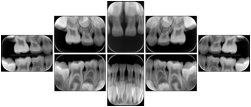

In most standard cases, images are oriented in structured layouts. These structured displays are useful to be shared between providers for reference purposes.

Table OO.1.1-1 shows structured display standard templates, where Viewset ID is based on the Japanese Society for Oral and Maxillofacial Radiology (JSOMR) classification provided by JIRA (Japan Medical Imaging and Radiological Systems Industries Association, www.jira-net.or.jp). Expected or typical teeth to be imaged location, region and designation codes are based on ISO 3950-2010, Dentistry - Designation system for teeth and areas of the oral cavity. For all the hanging protocols listed in OO.1.1-1, the value to use for Hanging Protocol Creator (0072,0008) is "JSOMR" and the value to use for Hanging Protocol Name (0072,0002) does not include "JSOMR" (e.g., "DL-S001A", not "JSOMR DL-S001A").

Table OO.1.1-1. Hanging Protocol Names for Dental Image Layout based on JSOMR classification